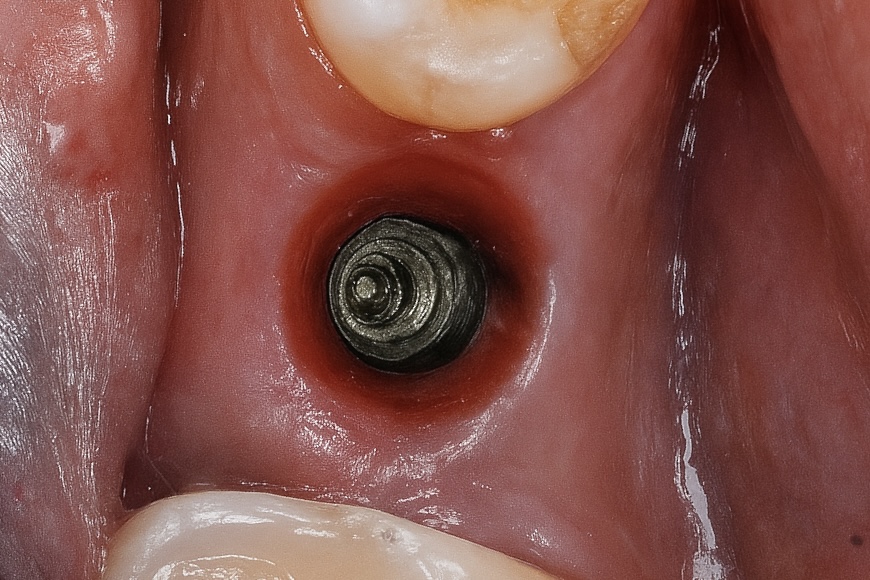

3️⃣ Healing and Soft-Tissue Maturation

After 8 weeks, the peri-implant mucosa showed healthy keratinized tissue with proper emergence form (Fig 2).